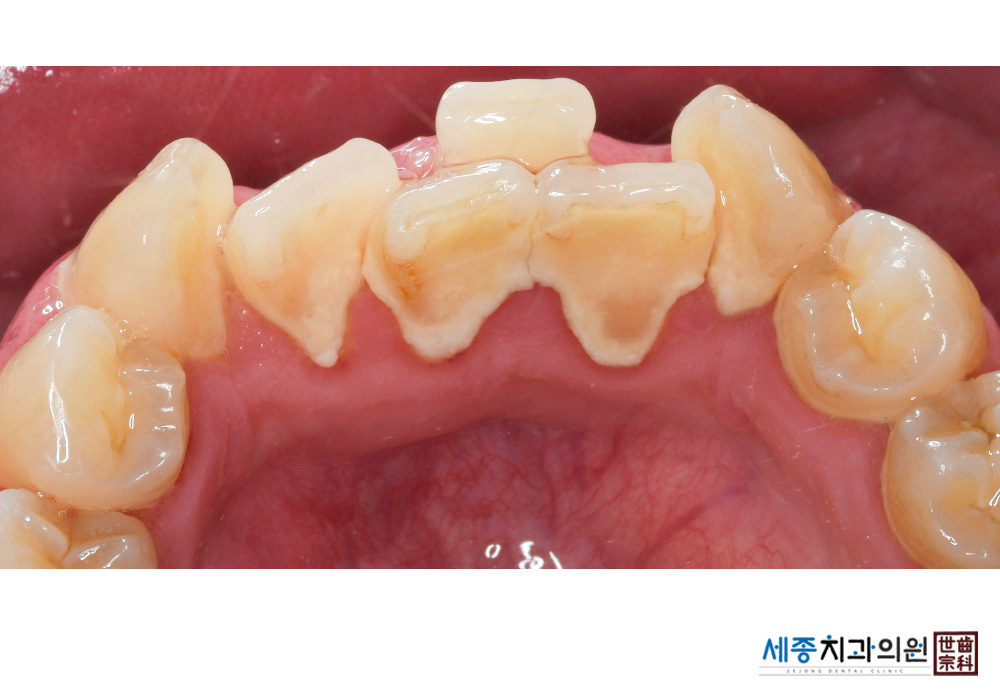

[스케일링] 치주질환 예방 스케일링

치료전 : 2020-02-03

치료후 : 2020-02-03

가글마취&저주파 스켈러를 사용한 스케일링